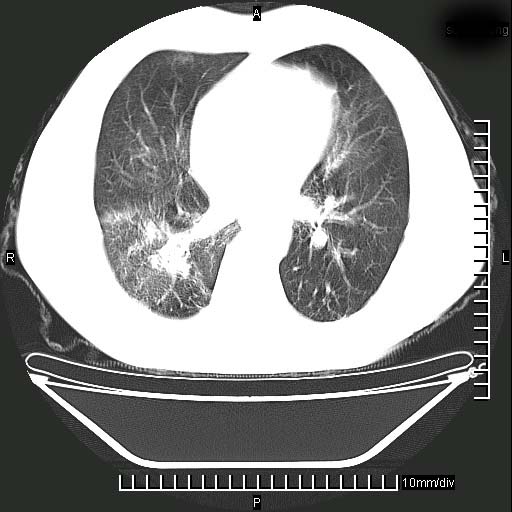

既往肺结核,近10几天,咳嗽,咳痰,右侧胸痛,疼痛较明显,右上肺斑块考虑结核灶胸膜粘连,增强,可惜动脉期没有定好,未见强化,可延迟4分后又见较明显强化,中心见低密度影,如果说结核是边缘强化,可这个灶强化的面积挺大的,让人很挠头。

延迟4分后